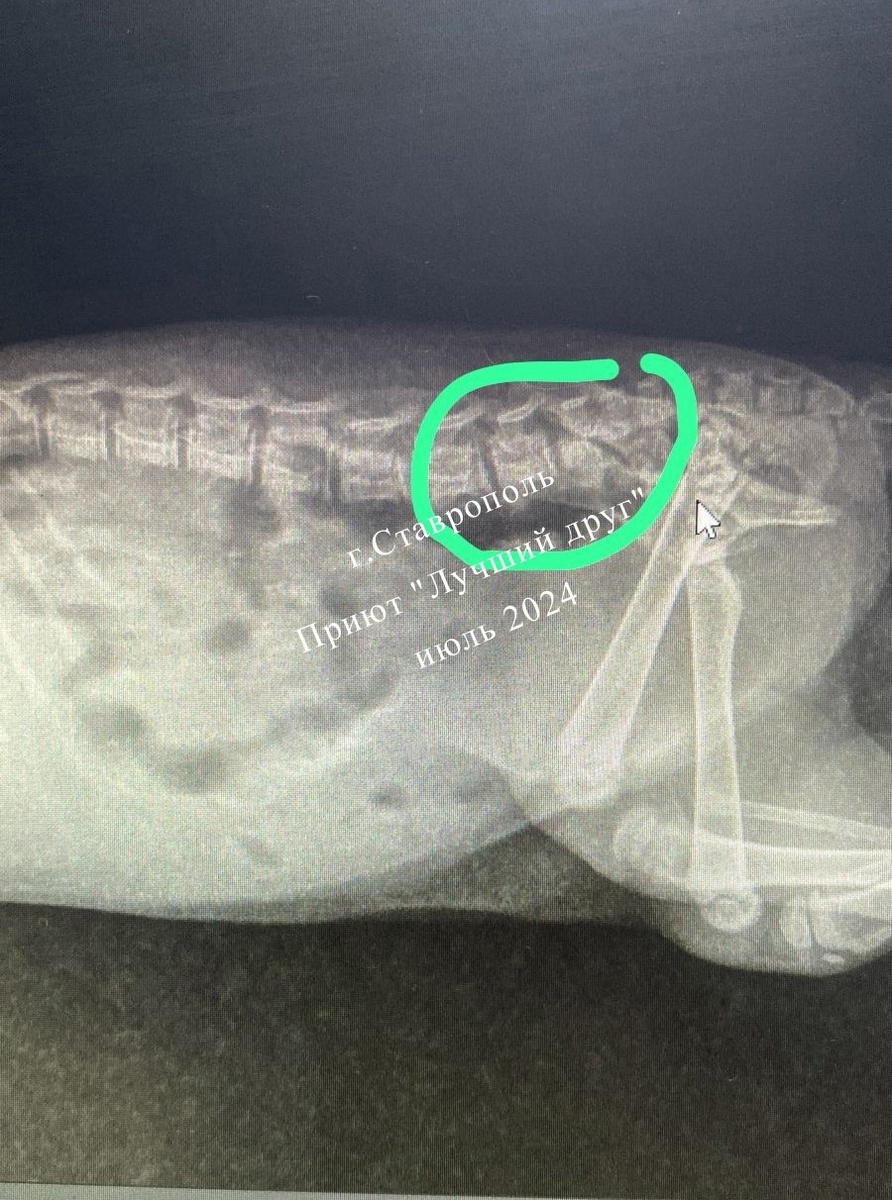

Вчера поздно вечером в клинику поступил травмированный котенок Булочка, на нее случайно наехал велосипедом ребенок. Котенок крохотный, вес велосипеда и мальчика большой, травмы у Булочки от этого столкновения, конечно, серьезные. В первую очередь пострадал позвоночник крохи (на рентгене обведено зеленой линией), нужно срочно делать МРТ, пока травма свежая и еще хоть что-то можно предпринять. МРТ в Ставрополе не делают, нужно везти в Краснодар, а это большие непредвиденные расходы... МРТ стоит 6 тысяч, анестезия примерно 2 тысячи и оплатить бензин на поездку около 5 тысяч. 12 тысяч нужно для обследования маленького котенка, который только жить начал, а уже пережил такую боль и ужас!

В первую очередь пострадал позвоночник крохи (на рентгене обведено зеленой линией), нужно срочно делать МРТ, пока травма свежая и еще хоть что-то можно предпринять. МРТ в Ставрополе не делают, нужно везти в Краснодар, а это большие непредвиденные расходы...